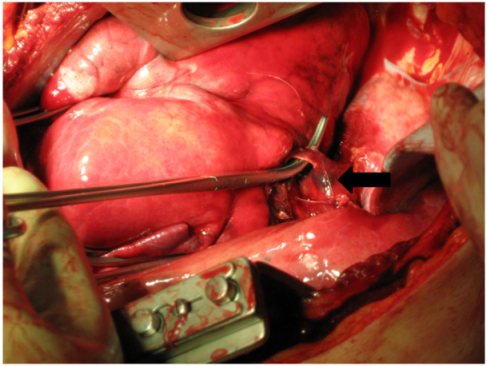

Upon arrival at the emergency trauma room a blood-soaked dressing showed. Through the drainage one liter of blood emerged and the bleeding was persisting (Figure 1 [Fig. 1]). Despite of pressure infusion of two red cell concentrates and several liters of ringer’s solution circulation could not be improved. That is why the patient was transferred to the operating room. During intubation with a double-lumen tube the blood pressure decreased and ventilation of the patient became difficult. On suspicion of a spontaneous tension pneumothorax on the left side (auscultatory breathing sounds only on the right side) a drainage was placed immediately in the second intercostal space on the left side (28 Ch). Air and blood emerged explosively through this drainage. After that, blood pressure increased and the ventilation improved (decrease in ventilation pressure). Simultaneously, sonography of thorax and abdomen was performed to exclude pericardial tamponade and intraabdominal bleeding. After left-lateral thoracotomy in the 5th intercostal space there was a pleural cavity filled with clots of blood and a multiple perforated superior lobe with multiple contusions could be seen. From the shot hole blood poured massively. Additionally, a sagittal through-and-through wound in the inferior lobe and a shotgun pellet in the main stem of the pulmonary artery showed (Figure 2 [Fig. 2]). For bleeding control and prevention of pulmonary embolism the hilum, of the lung was immediately disconnected and suction was performed via cell saver. Because of the persistent diffuse bleeding, the pleural cavity was plugged temporarily with operating cloths. After quick resection of the superior lobe and release of the clamp on the hilum of the lung, the specific disconnection of the inferior lobe followed. The big shot channel was opened via linear cutter (“tractotomy”) and open vessels and bronchial tubes were ligated. Smaller superficial lesions could be sealed by argon beamer. The removal of the shotgun pellet from the pulmonary artery required a brief disconnection with following sewing-over with felt-laminated sutures. After removal of additional shotgun pellets from the hemorrhagic dorsal wall of the thoracic cavity, the prophylactic incision of the pericardium followed to exclude a lesion of the heart.

Figure 1: Tamponade and drainage of the left chest